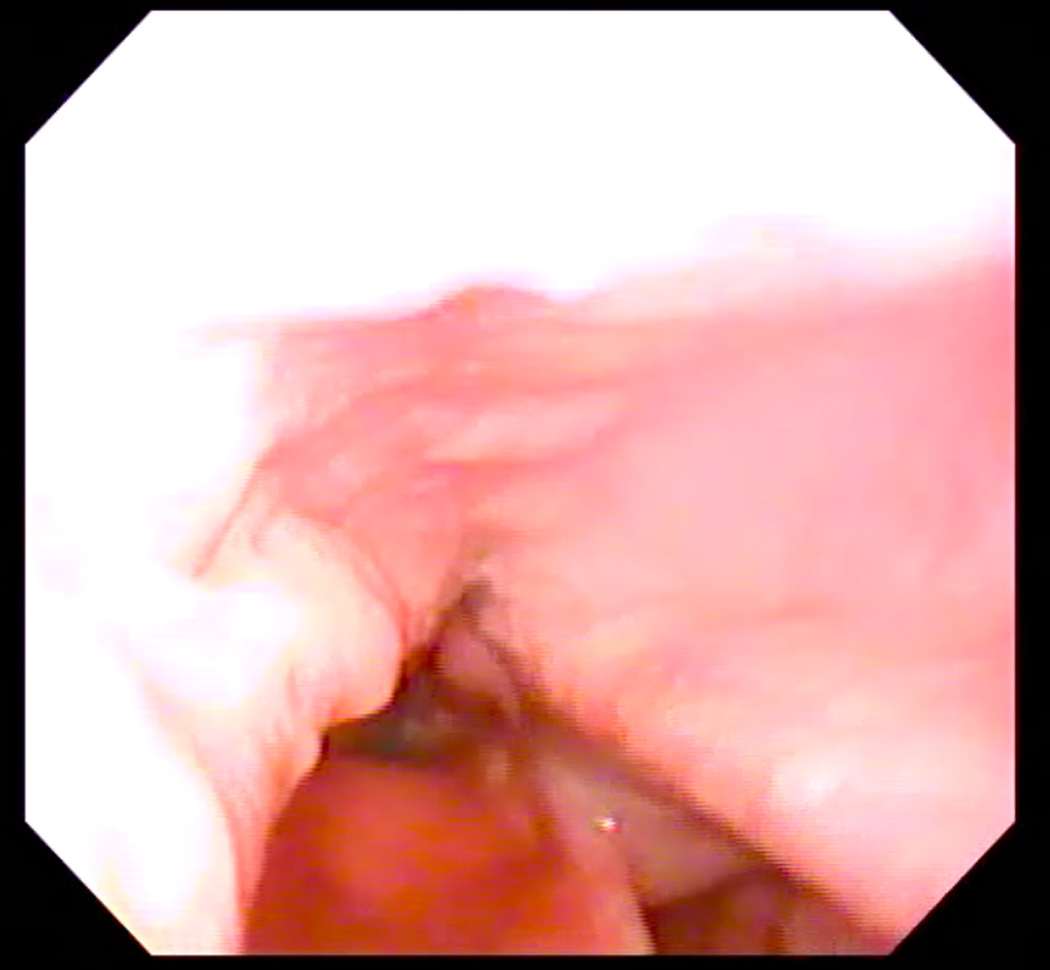

Eleven healthy subjects (six men, five women) age 22–30 years (mean age = 25) participated in this study under a research protocol approved by the Boston Medical Campus Institutional Review Board. Each subject first participated in a laryngoscopic exam and then two-planar dynamic MRI. Subjects were first taught how to produce the /i/ sound starting at their modal pitch, gradually elevating to their highest pitch, and then exerting effort once their highest pitch was attained to produce a forceful “ee” sound, as described by Bastian (1993). When they were able to perform the task perceptually, they were prepared for the laryngoscopic exam using two sprays of a nasal decongestant (neosyenephrine) and two sprays (0.1 ml) of 4% Lidocaine delivered via an atomizer through one nare. Following this, a flexible laryngoscope with an outer diameter of 3.4 mm was passed through the anesthetized nare. The scope was positioned just above the tip of the epiglottis for viewing the hypopharynx. Subjects were again provided with instructions for performing the EPG during the exam. One to three attempts were needed to achieve an acceptable EPG, as judged endoscopically as well as perceptually (see Figure 1, Panels A and B). Each subject completed the exam first in seated and then supine position in order to emulate the required posture for the MRI.

Figure 1.

A: Endoscopic image of hypopharynx at rest. B: Endoscopic image of effortful pitch glide (EPG) illustrating medialization of pharyngeal walls.